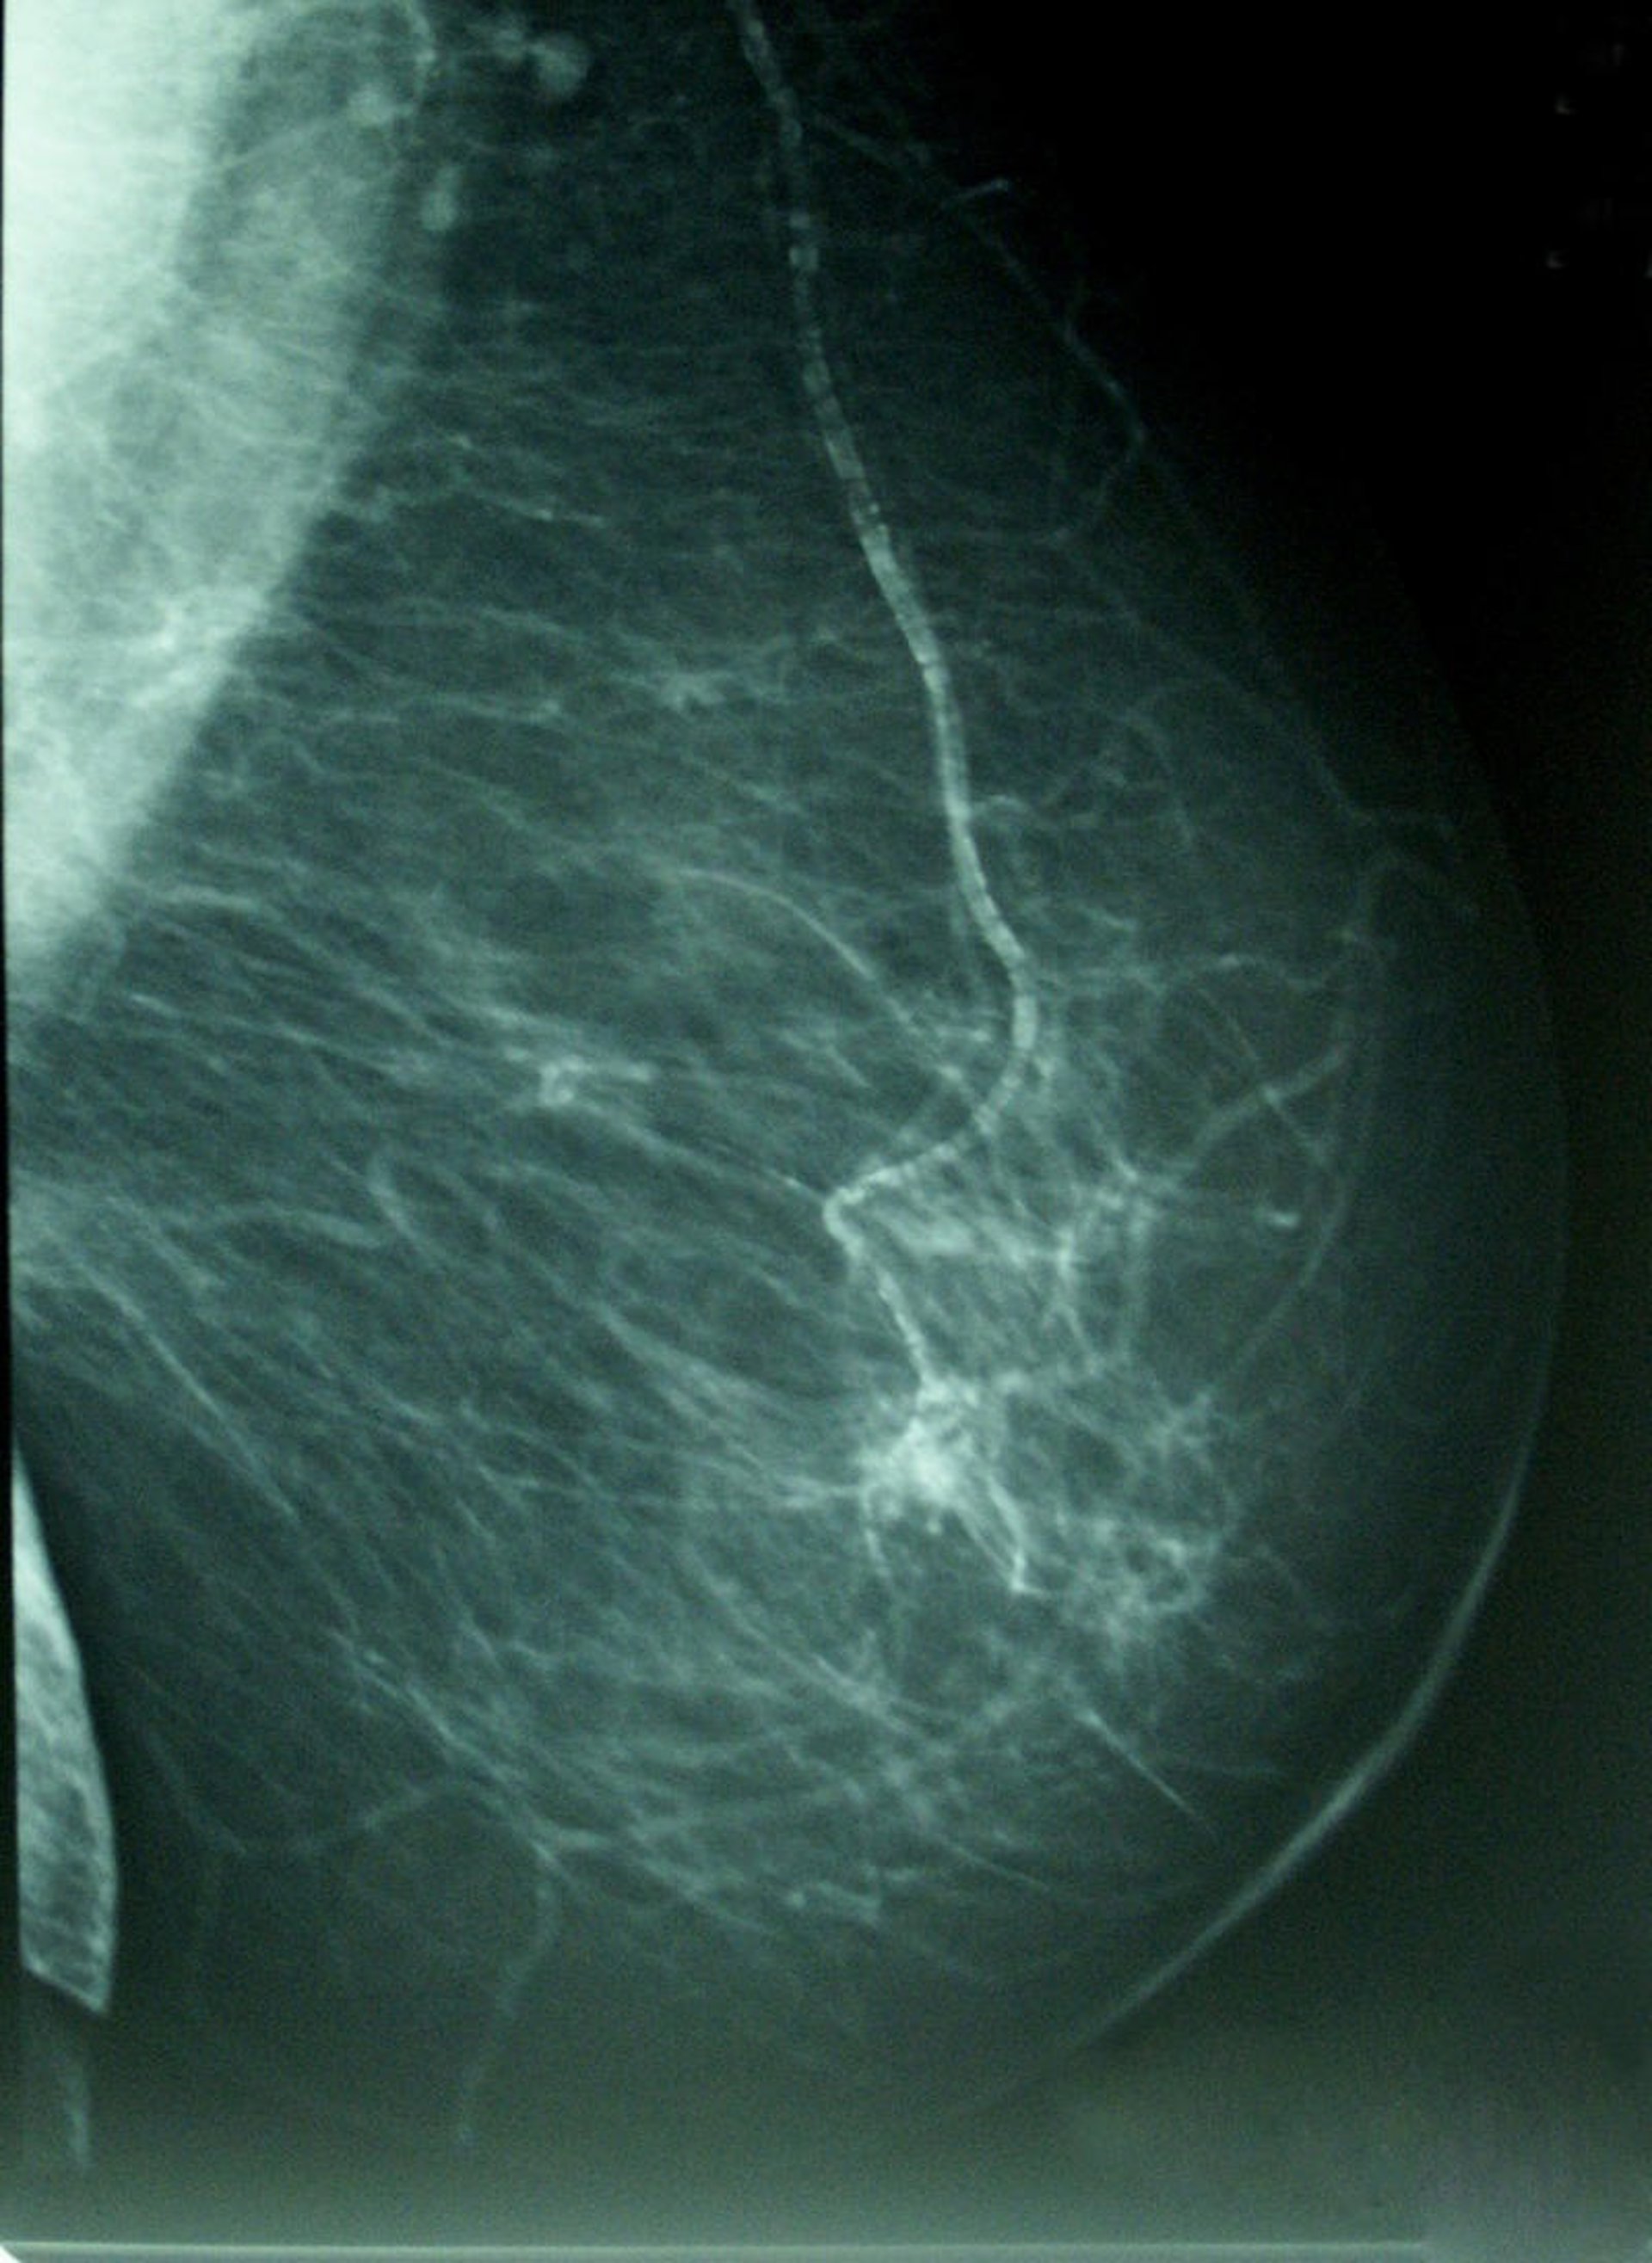

Por eso, ha destacado las campañas de prevención y de diagnóstico precoz de la Región de Murcia y ha aconsejado a todas las mujeres comprendidas entre los 50 y 70 años que se hagan una mamografía.

En Murcia, gracias a dicha campaña de Prevención del Diagnóstico Precoz del Cáncer de Mama, hay unas 150.000 mujeres de entre 50 y 70 años que se hacen una mamografía cada dos años.

Es decir "que cada año la campaña tiene alrededor de 75.000 mujeres que se hacen una mamografía", ha explicado Navarrete, lo que ocurre es que no acude el 100 por cien, sino alrededor de un 75 por ciento, "por lo que se dejan de diagnosticar una cantidad significativa de cánceres por no acudir a realizarse la prueba".

Tras lo que ha hecho un llamamiento para que todas las mujeres de esas edades se hagan una mamografía porque el diagnóstico precoz "consigue que el tumor se detecte antes de que se palpe", es "la mejor manera de poder luchar contra esta enfermedad" y tiene mucha posibilidad de curación. Además, ha apostillado, en los últimos bienios, se han diagnosticado más de 235 casos en la campaña de prevención.

En este sentido, Navarrete ha resaltado en una entrevista concedida a Europa Press que la campaña de mamografías para las mujeres de entre 50 y 70 años "está totalmente cubierto" por el Sistema Nacional de Salud y por la Comunidad Autónoma de Murcia.